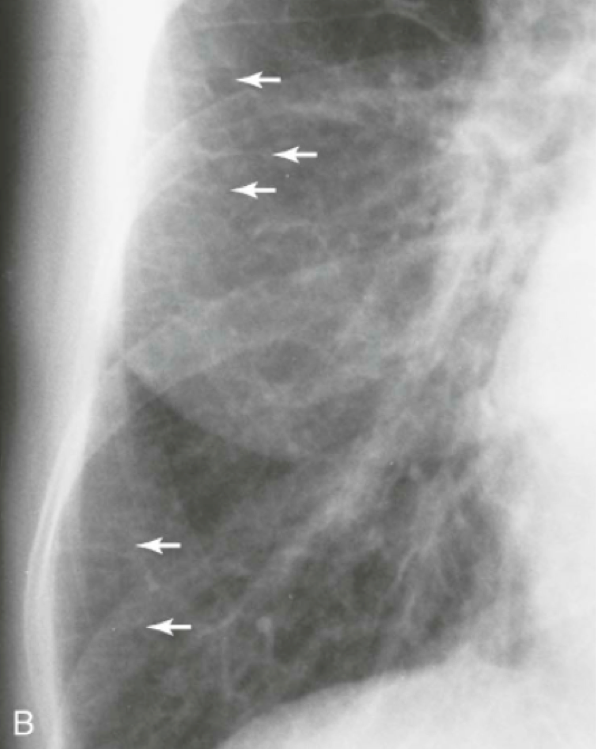

Question 22

Question

In "Kerley B Lines" , fluid may be seen in the interlobular septa at the basal aspects of the lung. Where is it always located and the position of it?

Answer

• inside the lungs; horizontal

• inside the lungs; vertical

• inside the ribs; horizontal

• inside the ribs; vertical

Question 23

In what diseases will you see this?

• COPD

• CHF

• Tuberculosis

• Pneumothorax